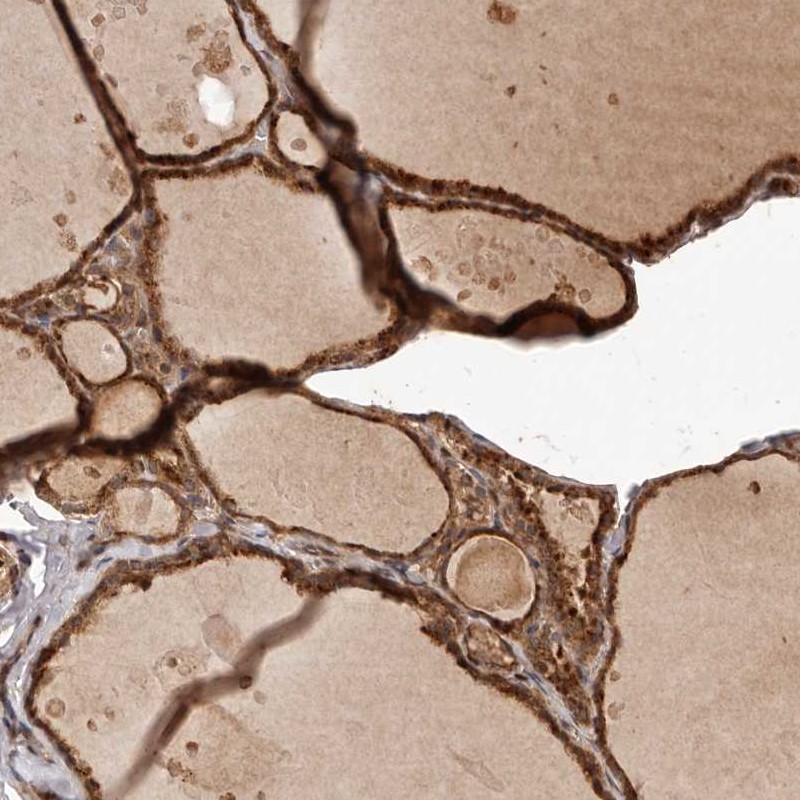

Immunohistochemical staining of human thyroid gland shows cytoplasmic positivity in glandular cells.